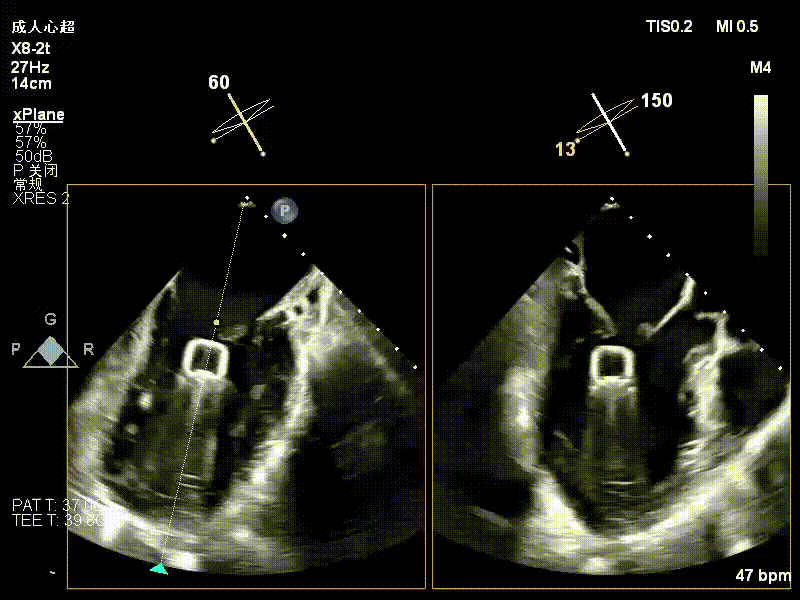

术中超声要点

术前术后对比图

术前

术后

术后,出院检查报告显示夹子位置固定,二尖瓣、三尖瓣及主动脉轻微反流,左房增大,左室内径正常上限,EF值正常下限(WMSI 1分)。